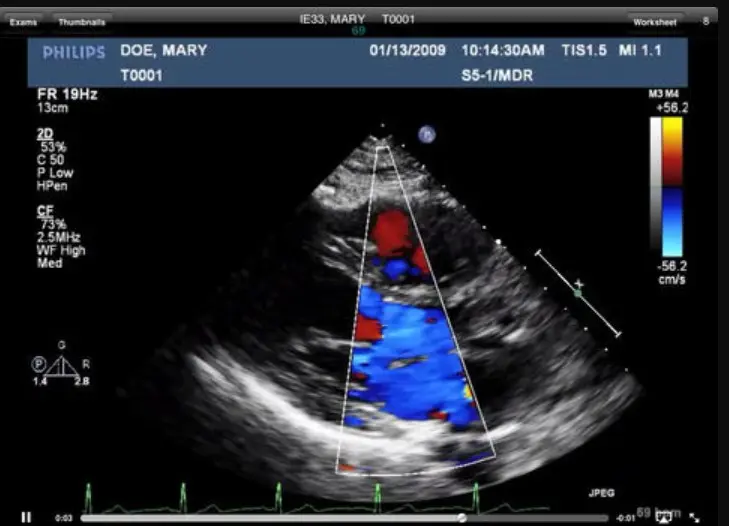

The software excels in medical imaging, supporting a wide range of modalities, including echocardiograms, vascular studies, and general ultrasound. UltraLinq allows healthcare providers to view, annotate, and analyze images directly within the platform, facilitating precise diagnoses and informed treatment plans. The platform’s customizable reporting tools further streamline clinical workflows, enabling the creation of detailed, specialty-specific reports tailored to the unique needs of each practice.